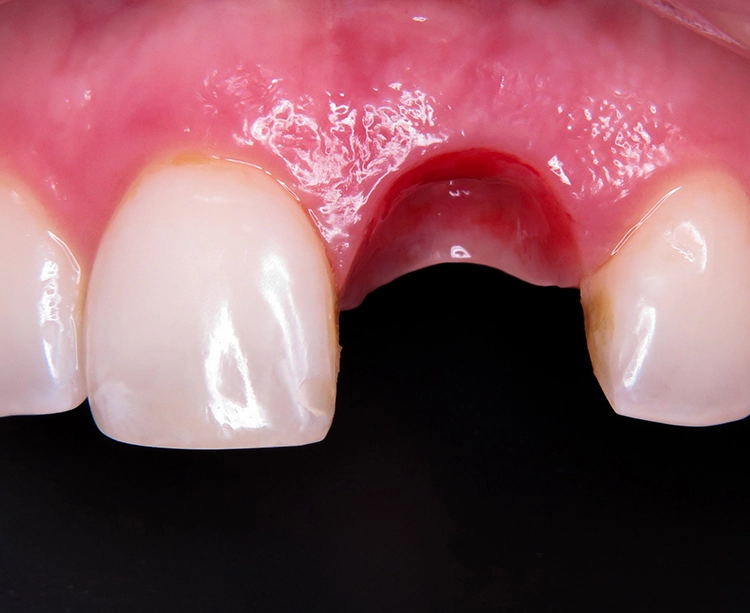

Zu den schwierigen Anforderungen im Frontzahnbereich gesellten sich hohe ästhetische Ansprüche. Die klinische sowie radiologische Diagnostik (Abb. 2) ergaben, dass der Versuch des Erhalts von Zahn 21 keine sichere Perspektive bot. Die Entscheidung fiel für die Extraktion des Zahnes. Um das Hart- und Weichgewebe bestmöglich vor der physiologischen Remodellierung nach der Extraktion zu bewahren, wurde eine Sofortimplantation geplant.

Mit dem sofortigen Einbringen eines Implantats in die Extraktionsalveole soll einer umfangreichen Knochenresorption und einem starken Weichgeweberückgang vorgebeugt werden [1,5,7]. Zudem ist bei einem lappenfreien Vorgehen das chirurgische Trauma gering, was dem ästhetischen Ergebnis (keine Narbenbildung) zugutekommt. Letztlich sind die vergleichsweise schnelle prothetische Rehabilitation und die reduzierte Anzahl von Behandlungssitzungen Argumente für dieses Therapieprotokoll.

Unter Lokalanästhesie wurde der beherdete Zahn 21 extrahiert und hierbei auf die maximale Schonung der vestibulären Lamelle geachtet. Die Entzündung konnte rückstandslos entfernt werden. Die Sondierung ergab eine intakte faziale Knochenlamelle (Abb. 6). Die frische Extraktionsalveole wurde als Implantatbett aufbereitet und das Implantat (BLX ø 4 mm, 14 mm) entsprechend der Planung dreidimensional im palatinalen Bereich der Alveole inseriert [3,6] (Abb. 7 und 8).